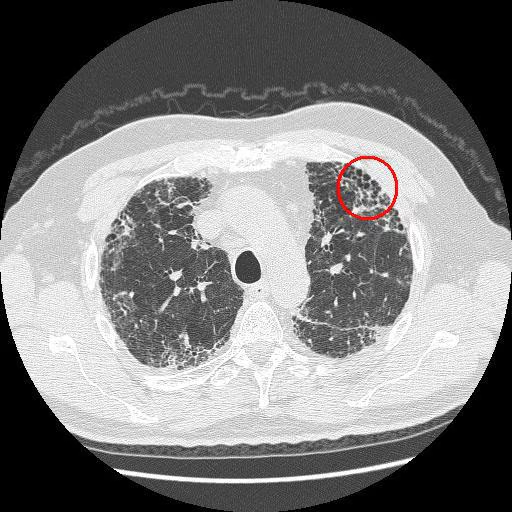

- High-Resolution CT (HRCT) of the chest is the key imaging modality.

- Typical Usual Interstitial Pneumonia (UIP) pattern on HRCT is diagnostic and includes:

- Subpleural, basilar predominant reticulation.

- Honeycombing (clustered cystic airspaces), with or without traction bronchiectasis.

- Typical UIP pattern findings

- Honeycombing: multiple cystic lesions within the lung parenchyma due to fibrosis

- Irregular thickening of intralobular septa

- Reticular pattern and mild ground glass opacity (GGO)

- Traction bronchiectasis (irreversible dilatation of the bronchi and bronchioles due to fibrosis)